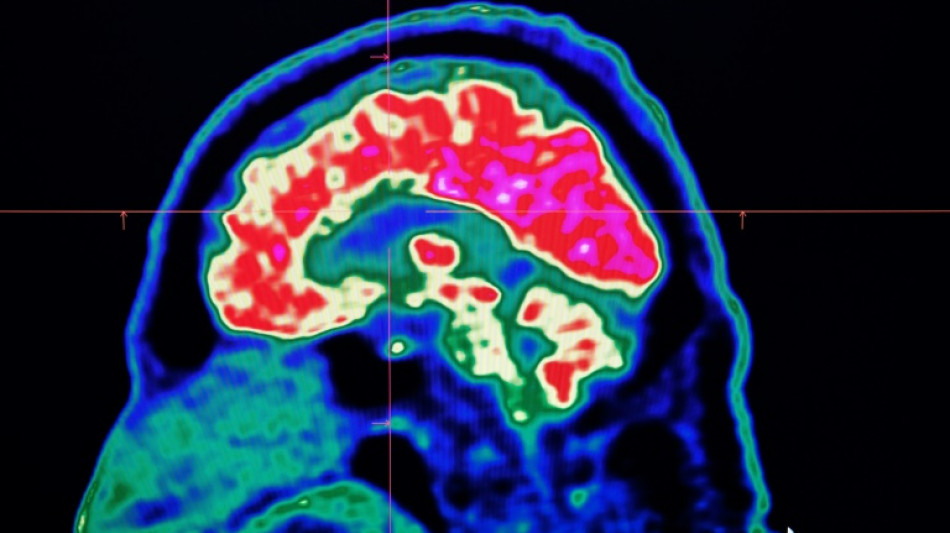

These mostly invisible pieces of plastic have been found everywhere from the top of mountains to the bottom of oceans, in the air we breathe and the food we eat. They have also been discovered riddled throughout human bodies, inside lungs, hearts, placentas and even crossing the blood-brain barrier.

The most prominent study looking at microplastics in brains was published in the journal Nature Medicine in February.

The scientists tested brain tissue from 28 people who died in 2016 and 24 who died last year in the US state of New Mexico, finding that the amount of microplastics in the samples increased over time.

The study made headlines around the world when the lead researcher, US toxicologist Matthew Campen, told the media that they detected the equivalent of a plastic spoon's worth of microplastics in the brains.

Campen also told Nature that he estimated the researchers could isolate around 10 grammes of plastic from a donated human brain -- comparing that amount to an unused crayon.